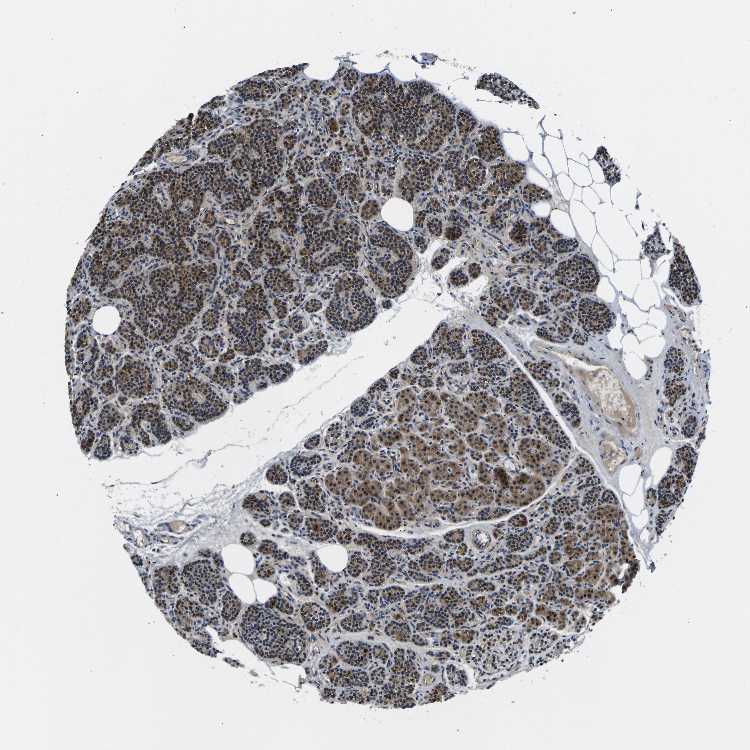

TISSUE PRIMARY DATA PARATHYROID GLAND Show tissue menu

PARATHYROID GLAND - Antibody stainingi

Antibody staining in the annotated cell types in the current human tissue is reported as not detected, low, medium, or high, based on conventional immunohistochemistry profiling in selected tissues. This score is based on the combination of the staining intensity and fraction of stained cells.

Each image is clickable and will lead to virtual microscopy that enables deeper exploration of all samples and also displays staining intensity scores, fraction scores and subcellular localization as well as patient and tissue information for each sample.

Antibody HPA015597Antibody HPA015598

Glandular cells MediumMedium